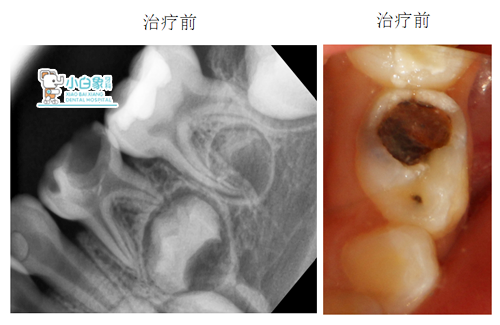

患者:###         女       4岁

主诉:左下后牙有洞月余。

现病史:左下后牙有洞,近期进食偶有疼痛,求治。

检查:74合面龋坏达髓角,探诊疼痛,温度测试反应迟钝,叩(-)牙龈无红肿。

X线片:低密度影像达髓角

诊断:74慢性牙髓炎

治疗方案:74根管治疗

治疗:74去腐露髓,封慢失一周。复诊开髓揭顶,拔髓,清理根管,冲洗,隔湿干燥,根管内置Vt,磷酸锌垫底,Z250充填。